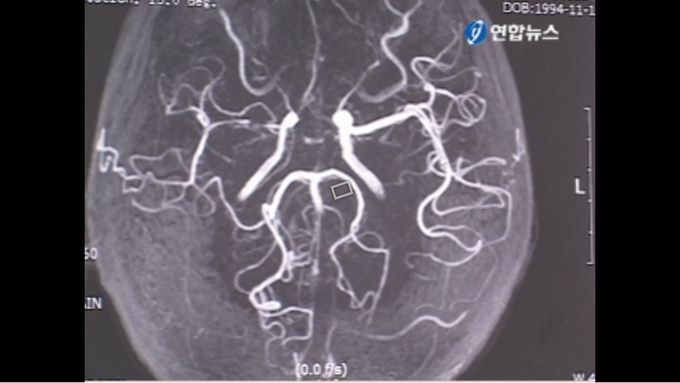

뇌동맥 내벽이 서서히 두꺼워지면서 말단 부위가 좁아지다가 막혀 혈류가 부족해져 ‘허혈성 뇌졸중’ 증상이 나타나는 질환인 ‘모야모야병(Moyamoya disease)’. 미세혈관 모습이 연기가 피어나는 모양과 비슷하다고 해 일본어로 ‘모야모야(もやもや)’라는 병명이 붙었다

이 질환의 이름은 일본의 스즈키 지로 교수가 1969년 붙인 병명으로, 뇌의 정상 혈관이 좁아지면 부족한 혈류량을 공급하기 위해 비정상적인 미세혈관이 자라나는데, 이 모양이 마치 연기가 피어오르는 모양과 비슷하다고 해서 붙여진 이름이다.